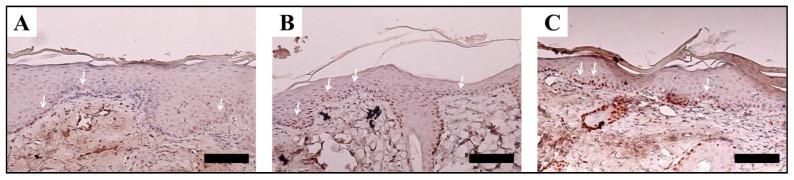

Silk fibroin (SF), an organic material obtained from the cocoons of a silkworm , is used in several applications and has a proven track record in biomedicine owing to its superior compatibility with the human body, superb mechanical characteristics, and its controllable propensity to decay. Due to its robust biocompatibility, less immunogenic, non-toxic, non-carcinogenic, and biodegradable properties, it has been widely used in biological and biomedical fields, including wound healing. The key strategies for building diverse SF-based drug delivery systems are discussed in this review, as well as the most recent ways for developing functionalized SF for controlled or redirected medicines, gene therapy, and wound healing. Understanding the features of SF and the various ways to manipulate its physicochemical and mechanical properties enables the development of more effective drug delivery devices. Drugs are encapsulated in SF-based drug delivery systems to extend their shelf life and control their release, allowing them to travel further across the bloodstream and thus extend their range of operation. Furthermore, due to their tunable properties, SF-based drug delivery systems open up new possibilities for drug delivery, gene therapy, and wound healing.